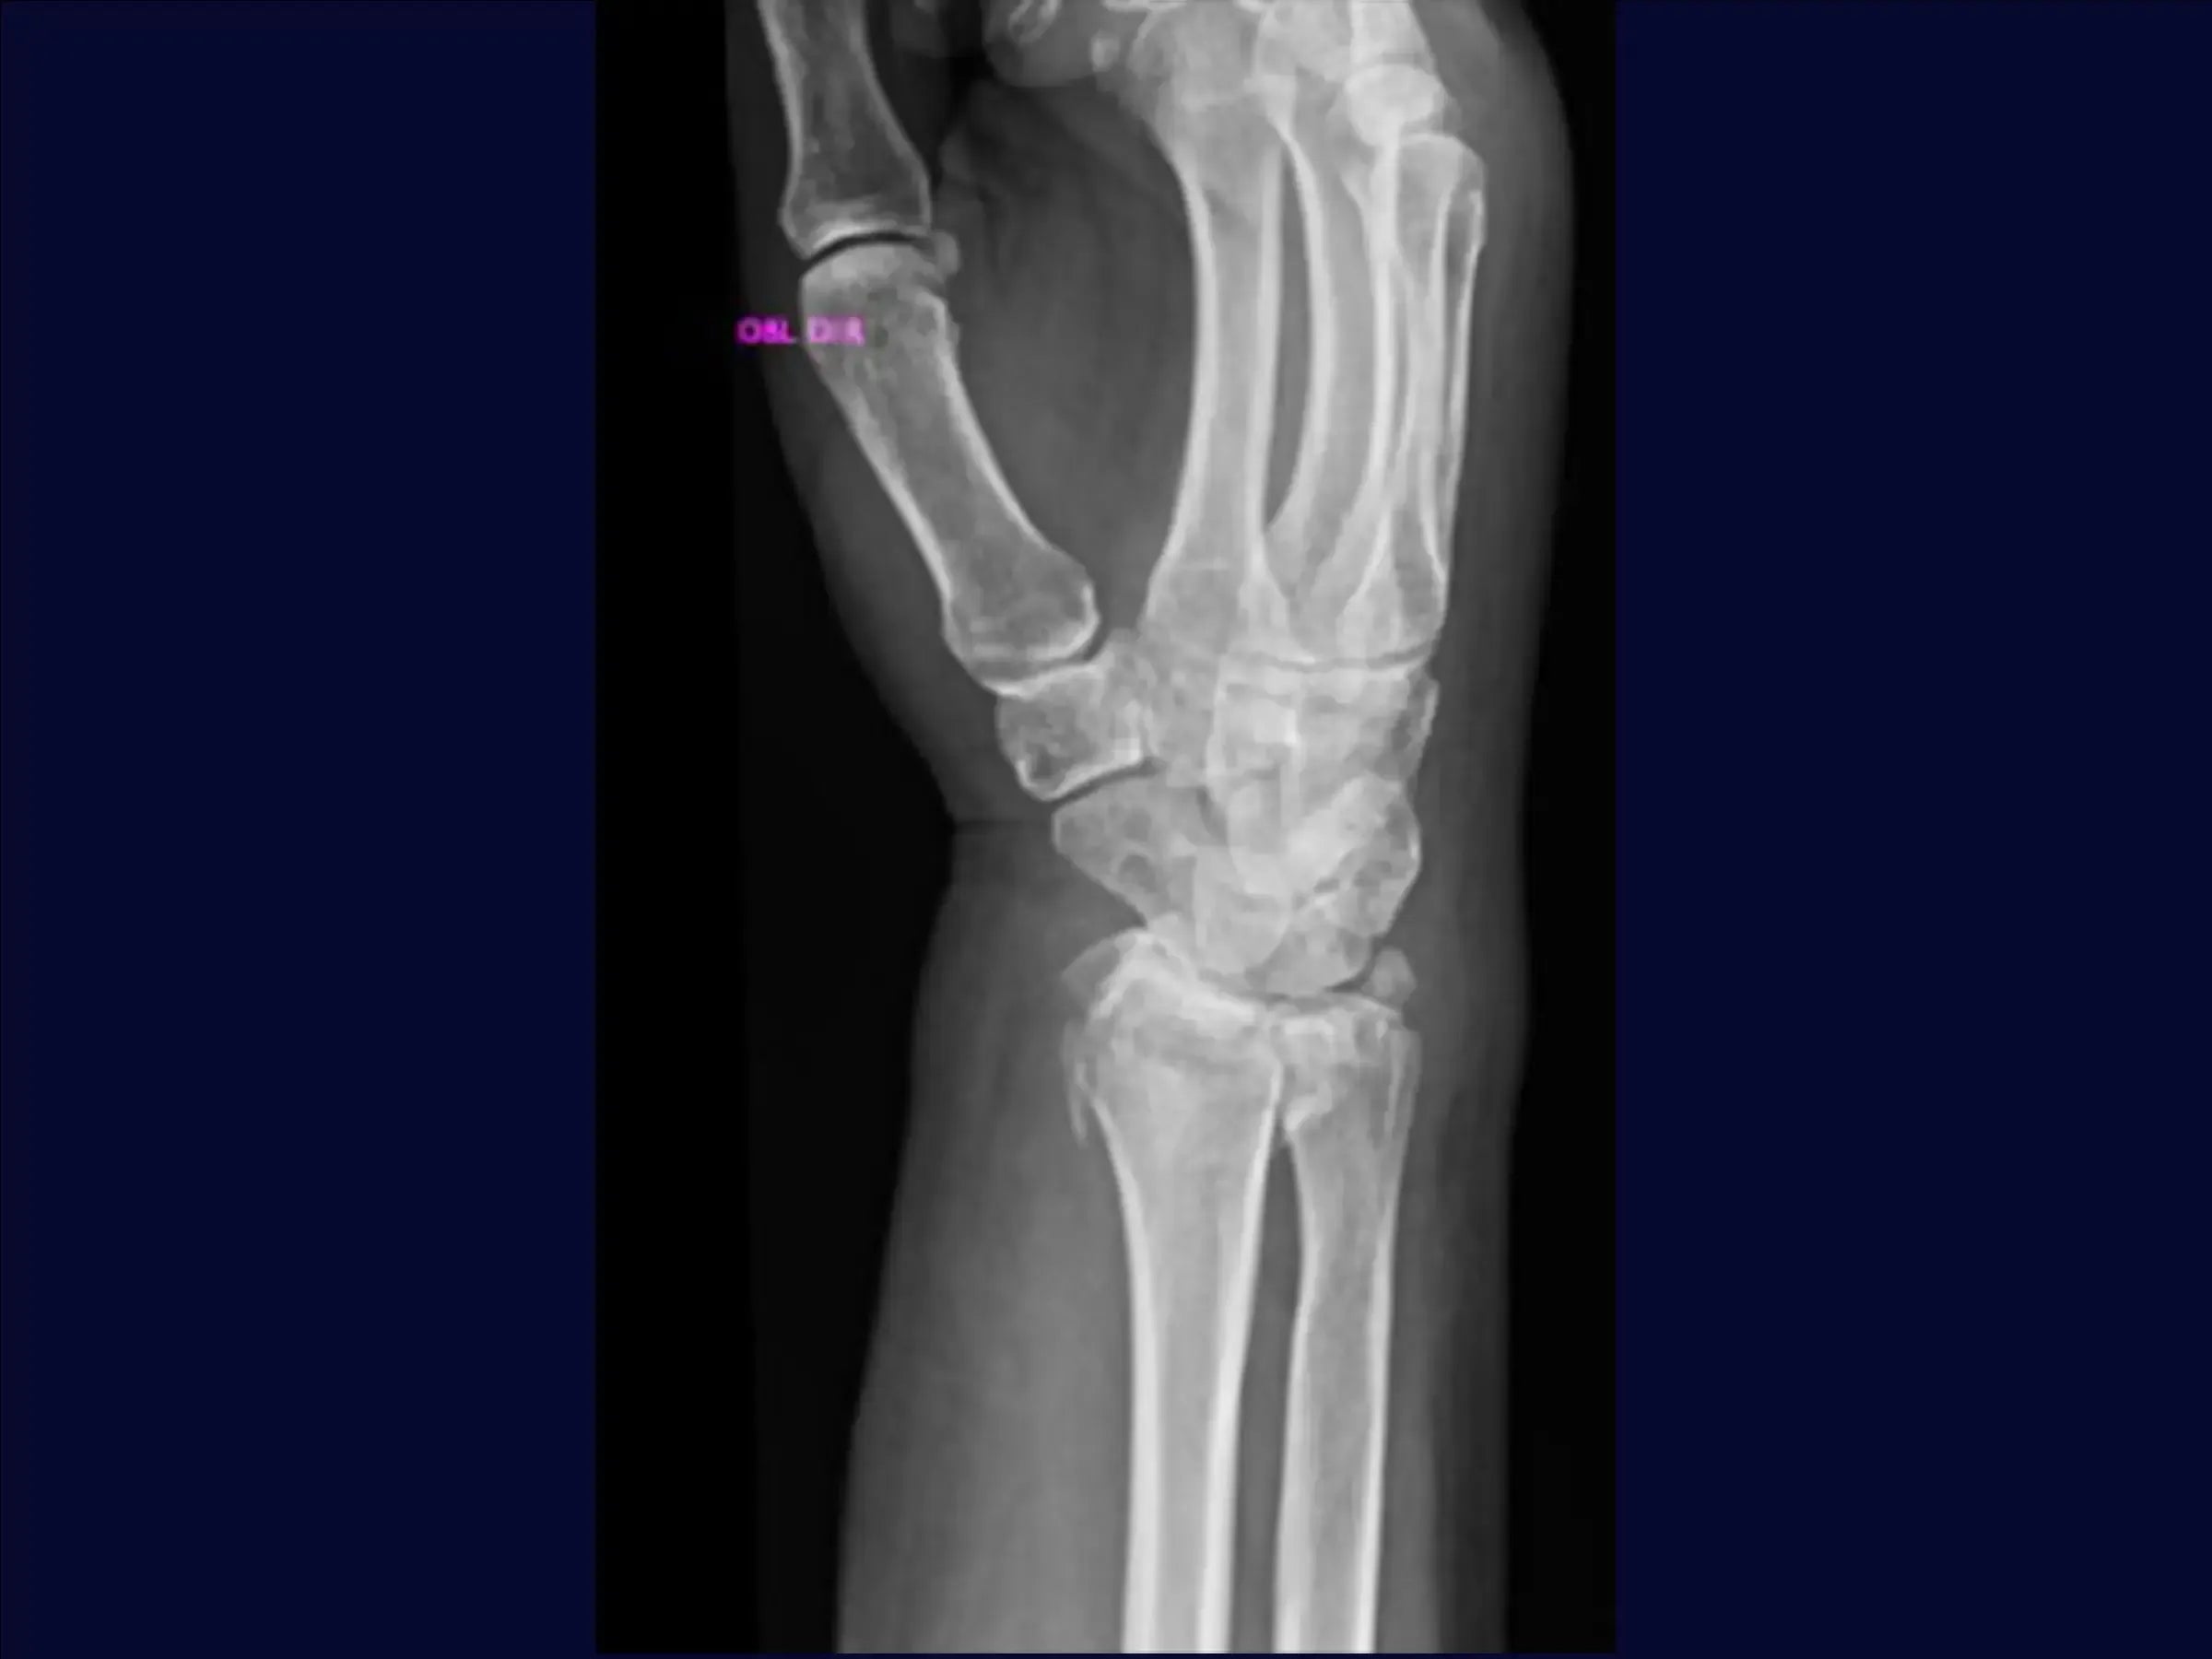

Domine o tratamento cirúrgico de fraturas do terço distal do rádio com cominuição dorsal e volar, e desvio dorsal. Este treinamento oferece uma imersão prática em uma abordagem volar, iniciando com fixação provisória da fratura, seguida pela dissecção cuidadosa dos planos e tendões, até a osteossíntese com placa, visando a redução anatômica e a estabilidade para a recuperação funcional do paciente.

- Tratamento cirúrgico de fraturas do terço distal do rádio com cominuição e desvio dorsal.

- Abordagem volar para redução e fixação.

- Fixação Provisória e Avaliação: O treinamento começa com a manobra de redução manual e estabilização provisória com fio de Kirschner de 2.5 mm, visando um bom posicionamento inicial da fratura.